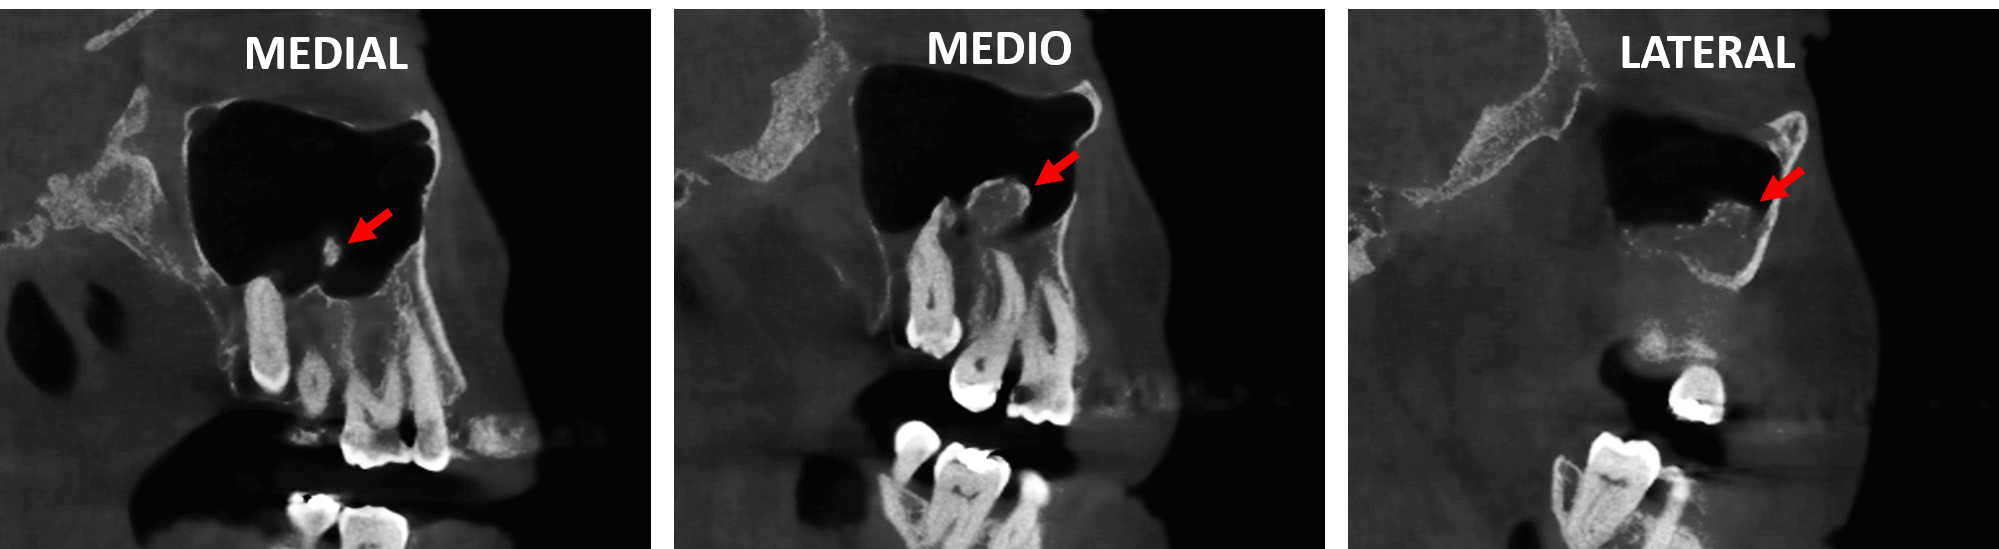

Fig.4

En cortes axiales (Fig.4) se observa la forma irregular de dicha estructura de densidad ósea en el interior del seno maxilar derecho compatible con una tumoración de origen benigno compatible con un Osteoma.